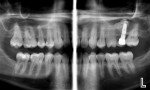

Some clinicians are not aware that they can take high-resolution (7-8 line pairs/mm) extraoral/panoramic bitewings. Dentists with pediatric patients may never have to put another image receptor in a child’s mouth again, and periodontists can take vertical bitewings without positioning problems. This is because several manufacturers now make panoramic machines that have bitewing programs. The disadvantage of the panoramic image for caries detection in the past has been inadequate line pair resolution and overlap of the contact points in the bicuspid regions. These deficiencies are now a thing of the past. One manufacturer (Planmeca, www.planmecausa.com) offers a patented technology called Selectively Compliant Articulating Robotic Arm (SCARA). The only machine to have a C arm on the top of its carriage, the bitewing acquisition is done robotically, with the patient in a typical panoramic position and the carriage moving inward toward the patient with a different start position to open contacts on most patients (Figure 1 through Figure 5). Of course, as with any dentition, if the tooth is ectopic or rotated, an additional image may be necessary to open the contacts. However, the quality of the image and ease of acquisition make this a very attractive technology. Looking carefully at the images, it is apparent that they are not only high-quality interproximal bitewing X-rays, but also high-quality periapical images from the canine to the molar region. Thus, with a digital panoramic machine capable of bitewing projections and producing excellent initial periapical views, the dose to the patient will be lower in most cases by eliminating unnecessary intraoral images. Although it is not a replacement technique, several dental schools in North America—including the Arizona School of Dentistry & Oral Health (ASDOH)—have adopted the protocol of using a panoramic and the extraoral panoramic bitewing/periapical projection as their initial radiographic examination. In addition, offices using this approach will find that there are fewer retakes and, therefore, less staff frustration related to radiographic procedures. At ASDOH, it has been found to reduce the number of full-mouth X-ray series, and intraoral and supplemental bitewing X-rays are needed only when indicated by selection criteria.

In addition to the possible reduction or even elimination of intraoral images for certain pediatric patients, the examples provided indicate that periodontists requiring vertical bitewings may also be interested in these contemporary panoramic machines.